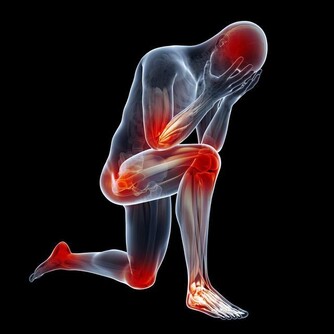

醫學認為,汗皰疹是濕疹的一種,是一種對稱性的、複發性的、多發生在手掌的水皰性疾病。汗皰疹發病有以下特點:

2、水皰為位於表皮深處的小水皰,米粒大小,半球形,略高於皮表,分散或成群發生在手上;

3、內含清澈漿液,發亮,偶爾可變渾濁;

4、小水泡多不自行破裂,破裂后可見圓領狀脫皮;

5、一般無瘙癢、疼痛等異常感覺。